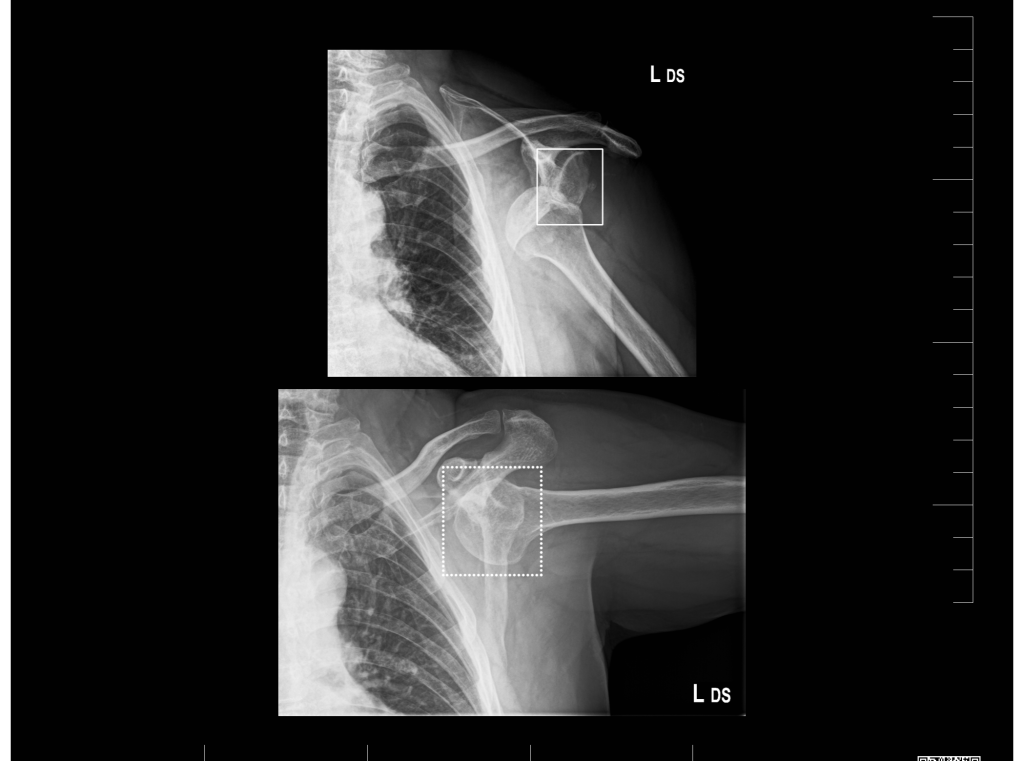

AI systém, ktorý je v nemocnici v prevádzke už niekoľko mesiacov, automaticky analyzuje röntgenové snímky a identifikuje prítomnosť zlomenín. V priebehu pár sekúnd dostane lekár spätný report. „Na obrazovke vidíme vyznačené miesto, kde je nejaká zlomenina alebo prasklina. Softvér dokonca automaticky hodnotí niekoľko projekcií. Nájde miesta, kde vyhodnotí zlomeninu, ale nájde aj miesta, kde je podozrenie, že ide o léziu,“ vysvetľuje prednosta.

Podľa námestníka Úseku medicínskych stratégií MUDr. Štefana Štolfu, PhD., ktorý je ortopédom na Klinike ortopédie a traumatológie pohybového ústrojenstva, je dôležité, aby lekár závery AI skontroloval. „Tu vidím zlomeninu jednoznačne a aj softvér ju presne identifikoval,“ vysvetľuje pri kontrole snímky pacienta. „Sú však prípady, kde je to nejednoznačné, AI indikuje, že na danom mieste môže byť zlomenina, a vtedy sa na to detailne pozrie rádiológ. Môže však ísť o starší úraz,  prípadne zavedený katéter. Umelá inteligencia si to všimne a upozorní lekára, pomáha to pri diagnostike najmä mladším kolegom, ktorí ešte nemajú toľko skúseností“.